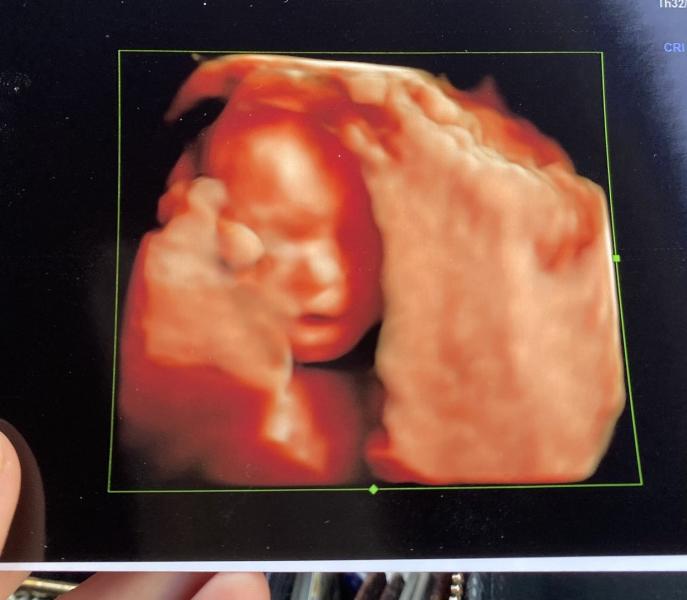

💝Доченька кажется по весу по серединке между старшей сестрой-дюймовочкой и братиком-богатырем🙃Предполагаемый вес 360 г. Срок по первому скринингу 21 неделя (пдр 8 августа), показатели на 20-21 неделю. Сидит на попе, как я и чувствовала последнее время😊На черно-белом фото узист поймал момент, где доченька засунула себе пальчики ног в ротик, развлекается😀